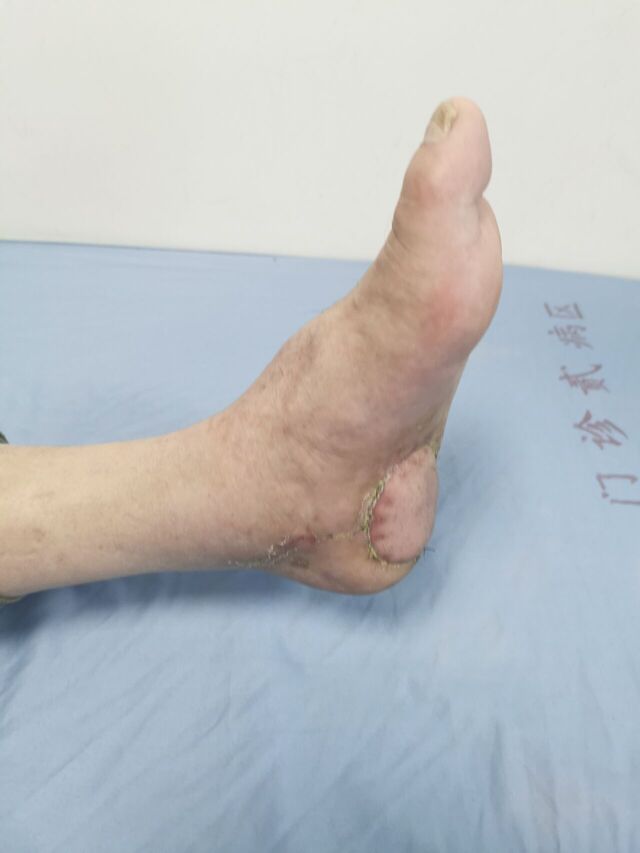

又帮足踝外科解决了一例足跟感染骨髓炎患者

皮肤缺损股前外侧皮瓣移植

可以下走路了

患者终于露出了久违的笑容